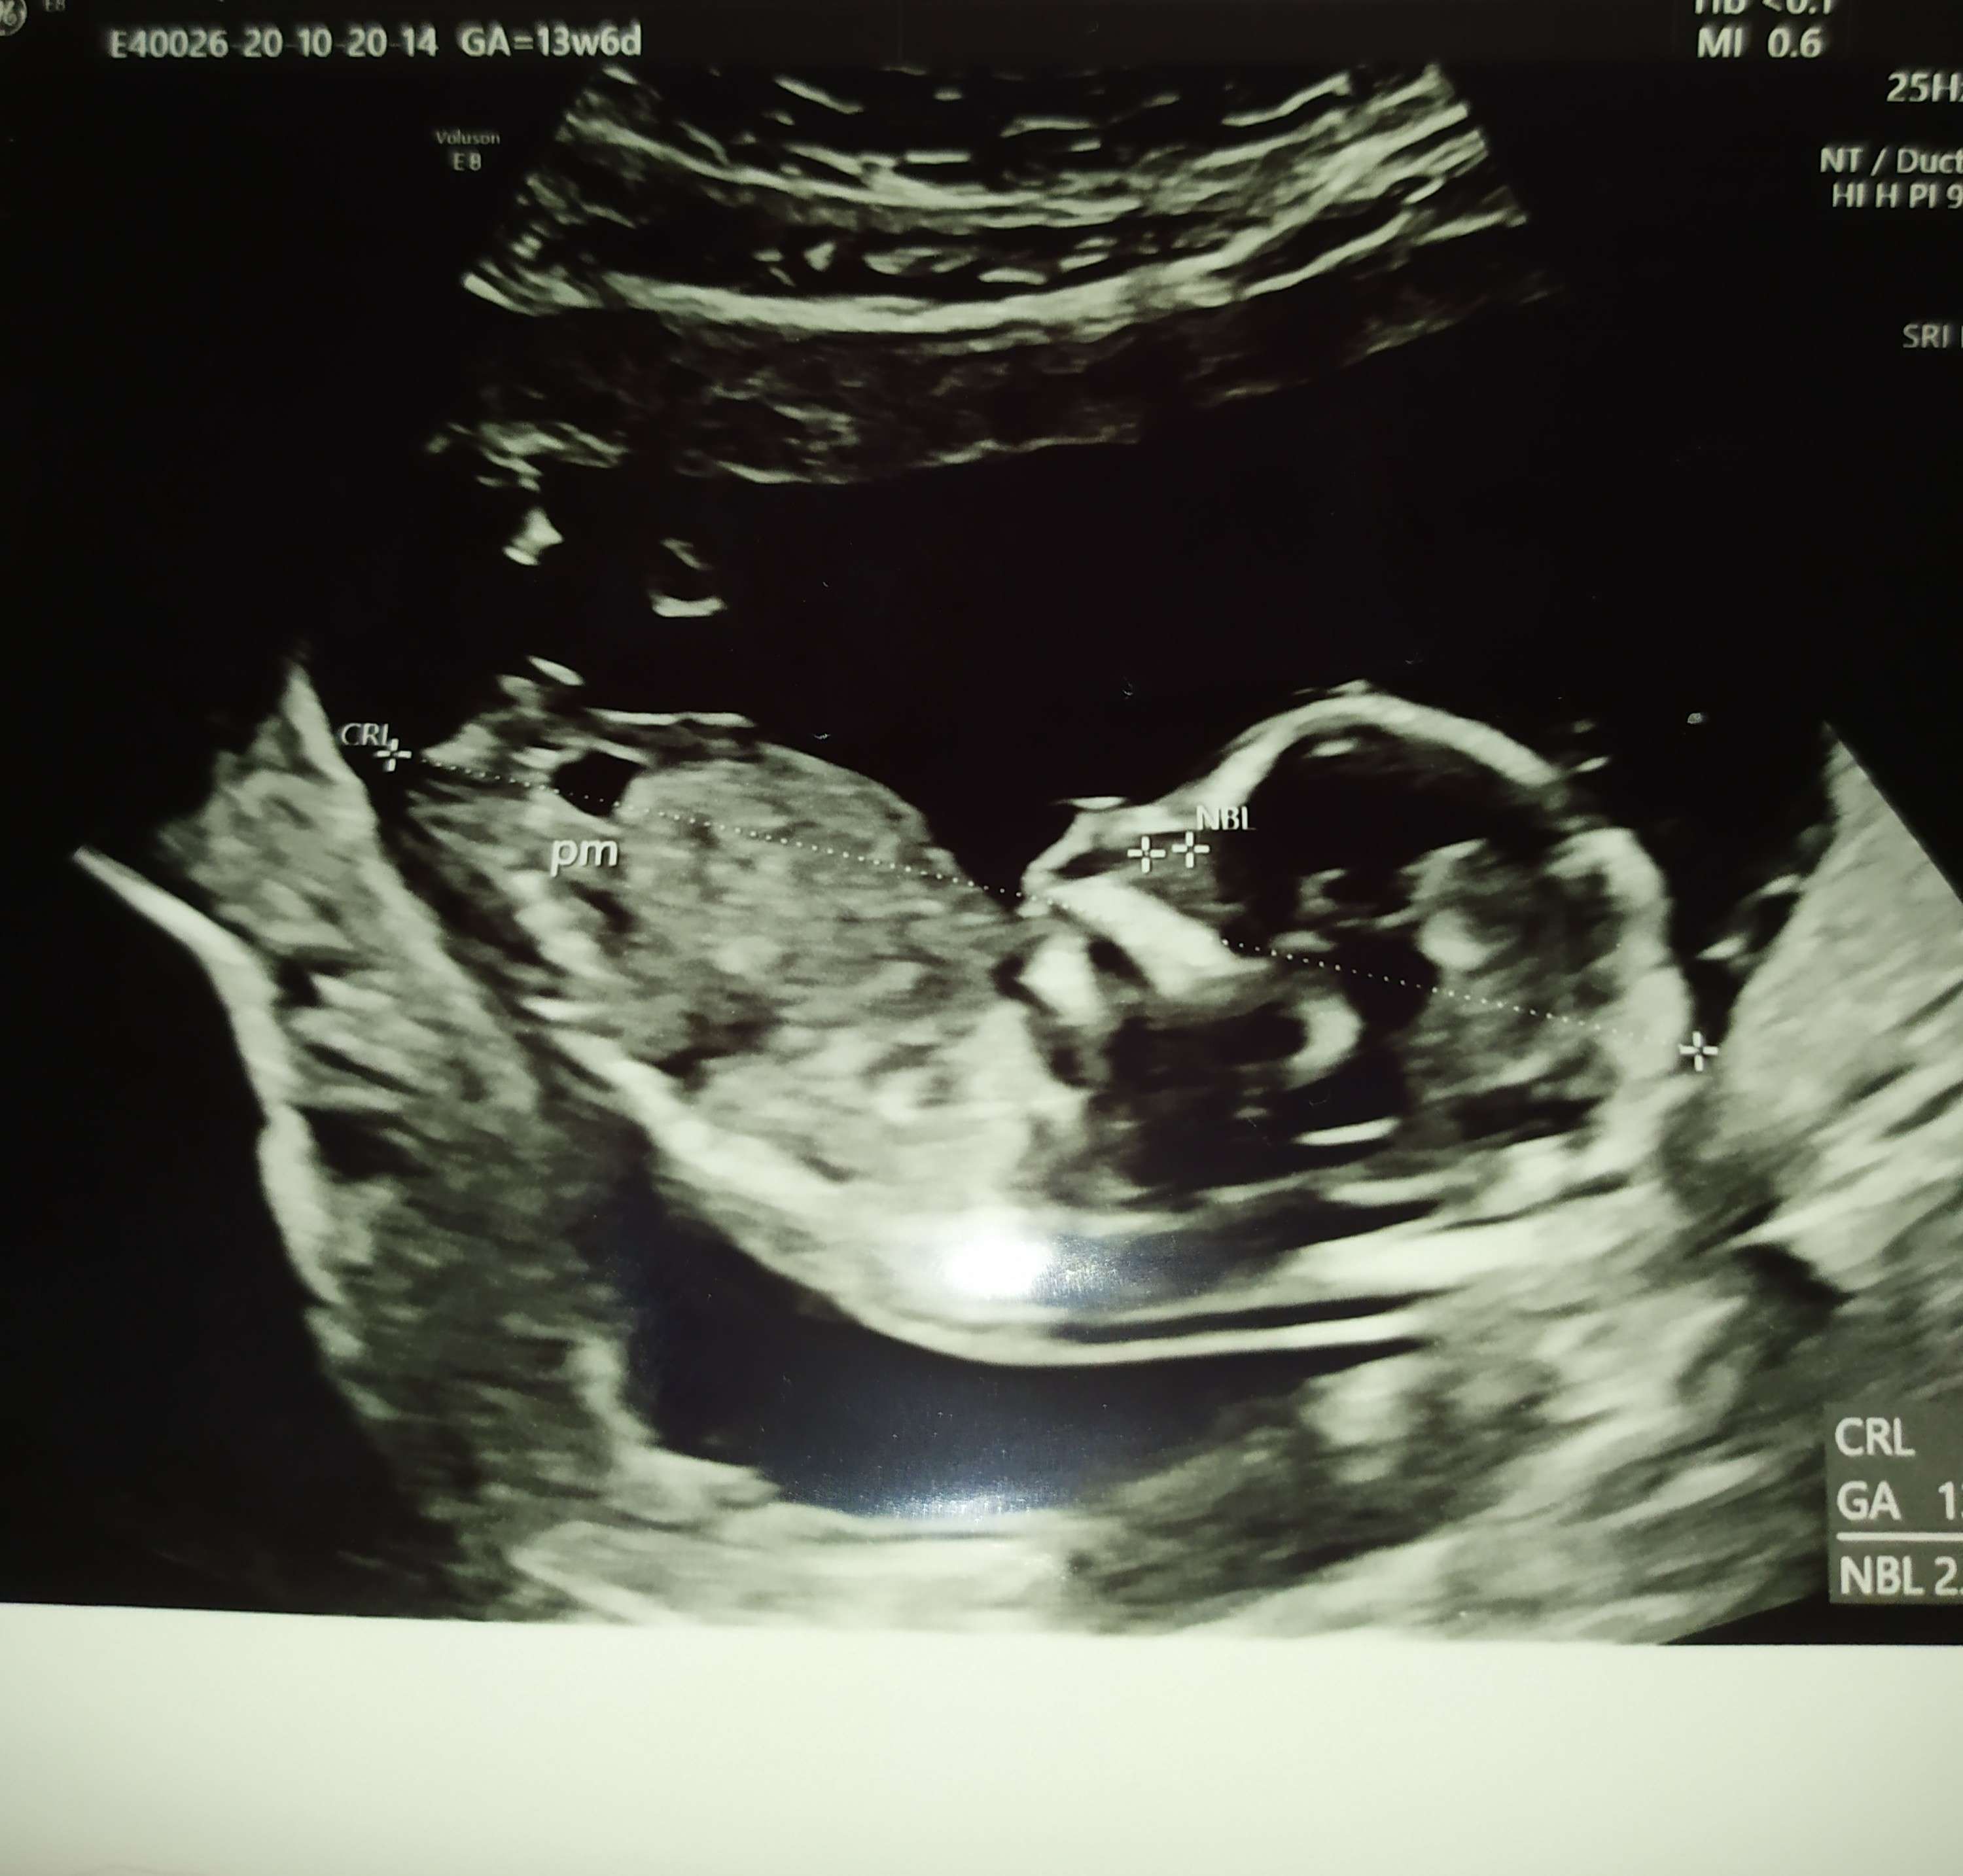

My po USG. Dzidzia książkowo rośnie, oczywiście wypinala dupsko, żebym tylko nie popatrzyła co ma w kroku 🙈😂

Wg wielkości dziecka niby 15tc, ale ogólne USG pokazuje na 14+5. Waży 105g🤔🤔🤔🤔 czy to jakoś nie za dużo? Czytałam ile na ten czas powinno mieć dziecko i piszą, że mniej. No, Ale lekarz powiedział, że rozwija się książkowo i Mu wierzę. A co mnie najbardziej ucieszyło , to to że miesniak zmalal 🥰 z 8cm do 7cm 😁

Witajcie, dzisiaj już trochę lepiej, leżę po śniadaniu żeby zostało ;) A zaraz do pracy. Odnośnie wczorajszego USG to lekarz był bardzo miły ( @Kamiśka :) nastawiałam się, że może być średnio ale chyba faktycznie miał wtedy gorszy dzień), wszystko pokazywał i objaśniał, nawet liczyliśmy palce u rączki [emoji2] Widziałam żołądek i pęcherz moczowy, serducho biło 152/min. Przezierność 1,8, ryzyko z wieku po USG spadło czterokrotnie :)Zobacz załącznik 1190837Zobacz załącznik 1190838Zobacz załącznik 1190839